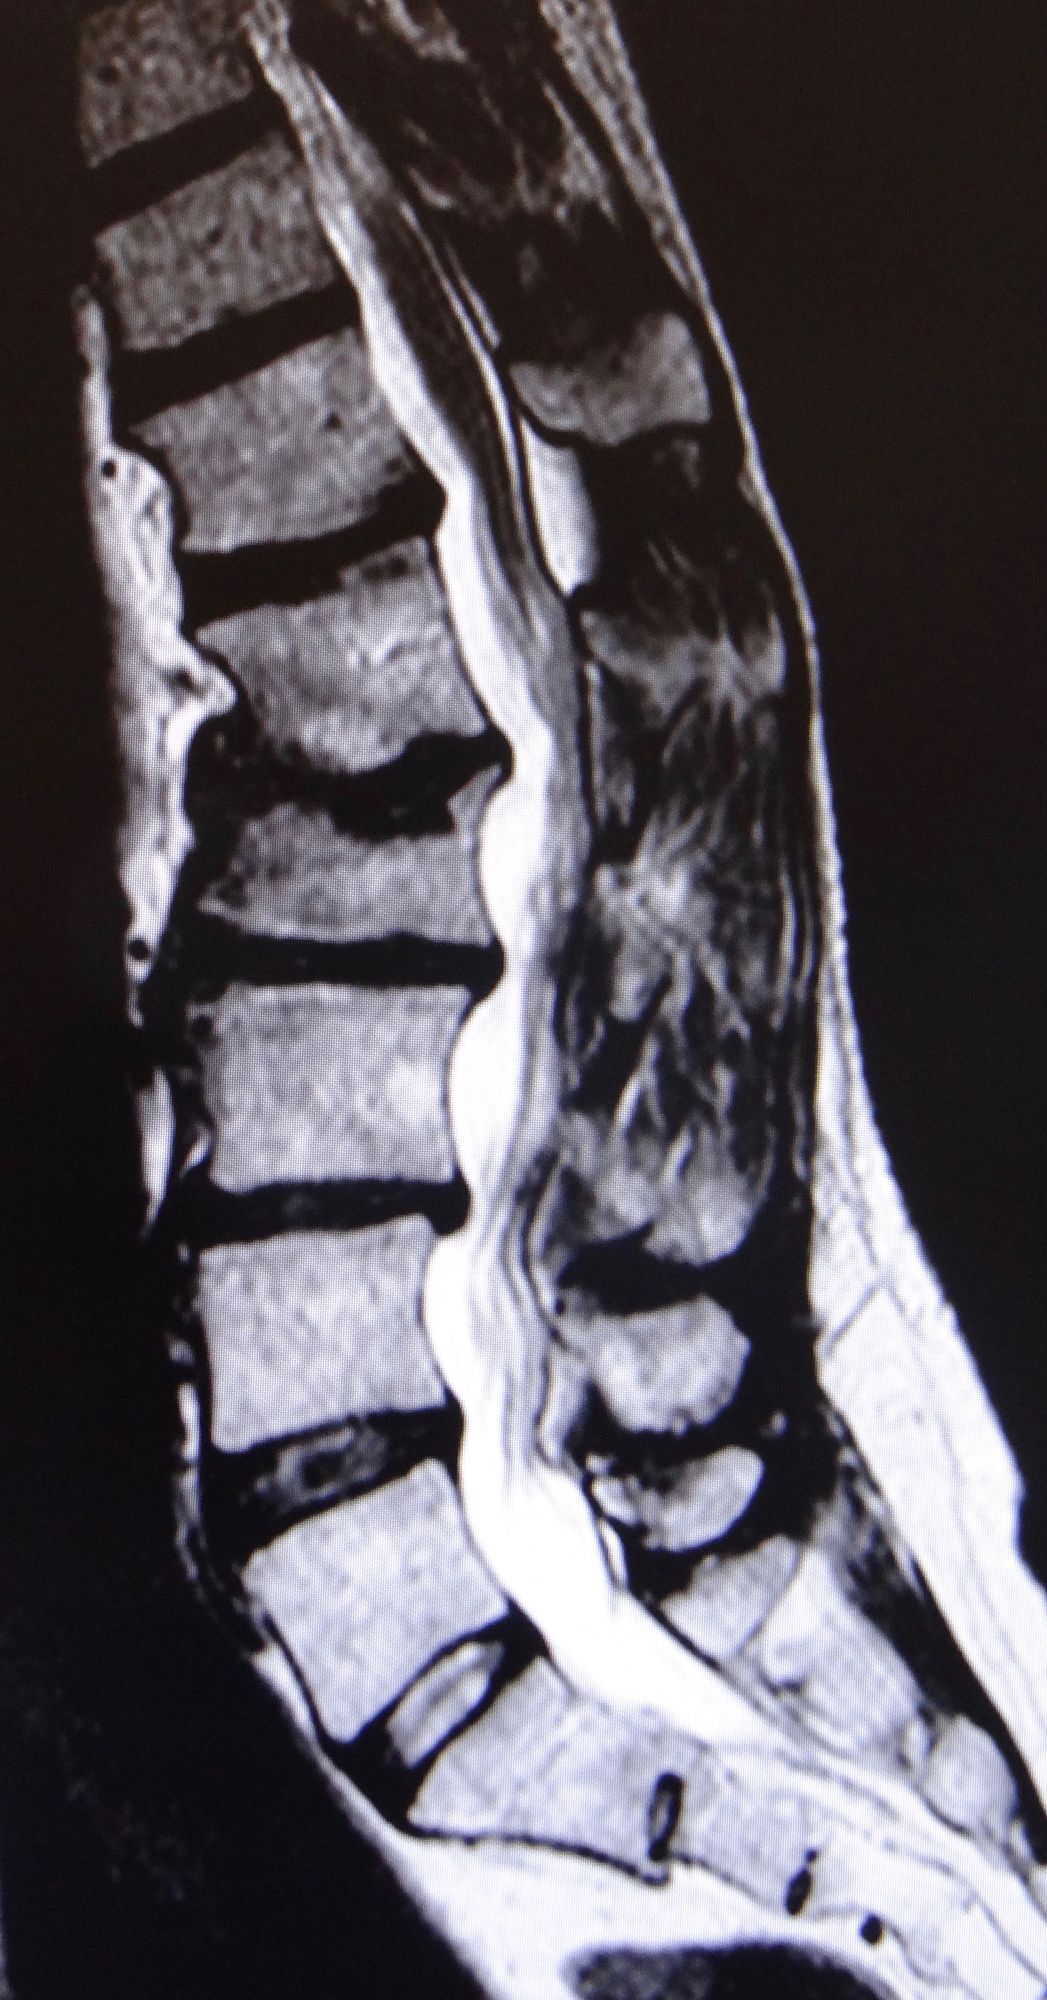

L’hernie discale est en lien avec l’usure du disque intervertébral, se trouvant entre deux vertèbres. Suite à un traumatisme ou un phénomène dégénératif par usure, du matériel discal provenant du cœur du disque fait sailli dans le canal rachidien et vient comprimer une racine nerveuse provoquant, entre autres, la fameuse sciatique (radiculopathie).

En effet, les symptômes provenant d’une hernie discale, sont une douleur au niveau du dos (lombalgie) avec irradiation de la douleur dans la jambe jusqu’au pied (sciatalgie). Des signes sensitifs, tels que des fourmillements, diminution de la sensibilité dans les jambes ou les pieds sont souvent associés. Il apparaît également, parfois, une perte de force dans les membres inférieurs, provoquant des difficultés à la marche. Dans de rares cas, il peut arriver des troubles sphinctériens, se traduisant par une incontinence urinaire ou fécale (perte d’urine ou de selles involontaire).

Le traitement d’une hernie discale consiste, dans la majorité des cas, au repos associé aux médicaments antidouleurs ( anti-inflammatoires, dérivés de la morphine, etc.), ce qui permet d’aboutir à une guérison spontanée. La douleur dans la jambe tend à disparaître relativement rapidement, alors que la faiblesse ou les troubles sensitifs peuvent perdurer.

Dans les cas de déficit moteur et/ou sensitif, ou de persistance/majoration de la douleur, une chirurgie de décompression du nerf est proposée. L’intervention consiste en une microdiscectomie (curetage du disque) avec résection de l’hernie.

C’est une maladie chronique progressive touchant la moelle épinière. En effet, en raison d’un rétrécissement du canal rachidien (le plus souvent au niveau cervical) par de l’arthrose et des ostéophytes (bec de perroquet) ou un phénomène compressif (hernie discale, kyste, tumeur,…) réduisant le diamètre du canal rachidien, la moelle épinière souffre.

Les symptômes se manifestent par une faiblesse progressive des quatre membres, touchant plus particulièrement les mains avec une perte de la dextérité des doigts, des troubles de la marche, une incontinence urinaire, rarement fécale, et peut évoluer vers la paralysie des bras voire des jambes. C’est une maladie qui évolue lentement dans le temps, sur plusieurs mois, voire années, mais qui peut parfois se décompenser rapidement lors de chute avec mouvement brutal de flexion et extension cervicale.

Le traitement consiste, dans la plupart des cas, en une chirurgie de décompression de la moelle épinière par discectomie cervicale antérieure et mise en place d’une cage avec plus ou moins une plaque/vis stabilisatrice. Malheureusement, il n’existe pas de traitement conservateur, excepté le soulagement des douleurs. Il est important d’opérer rapidement au moment du diagnostic afin d’éviter une aggravation de la faiblesse des 4 membres.

C’est un rétrécissement (sténose) du diamètre du canal rachidien au niveau cervical ou lombaire. C’est une maladie progressive liée à des phénomènes dégénératifs tels que arthrose, ostéophytes (bec de perroquet), dégénérescence du disque vertébral le plus souvent en lien avec l’âge, qui aboutissent à une diminution du diamètre du canal ou passe la moelle épinière (cervical, dorsal) et les nerfs (lombaire).

Les symptômes diffèrent en fonction de la localisation du canal étroit. En effet, au niveau cervical, voire dorsal, les patients présentent des signes de myélopathie (cf. Chapitre myélopathie). Au niveau lombaire, le symptôme pathognomonique est la claudication neurogène, qui se manifeste par des douleurs dans les deux jambes, exacerbées lors de la marche, avec un périmètre de marche nettement diminué. Les douleurs diminuent typiquement en positon assise ou couchée. Il est très rare que des atteintes sensitives ou motrices sous forme de diminution de la sensibilité ou faiblesse dans les jambes apparaissent.

Le traitement est conservateur, associant une modification du stress sur la colonne vertébrale, des médicaments antidouleurs, de la physiothérapie et des infiltrations épidurales (espace entre les nerfs et l’os) sous Ct-scanner pour diminuer les douleurs et l’inflammation. Si les douleurs persistent, malgré ce traitement, une chirurgie de décompression par recalibrage du canal lombaire ou cervical pour assurer un espace suffisant aux structures nerveuses, est effectué.